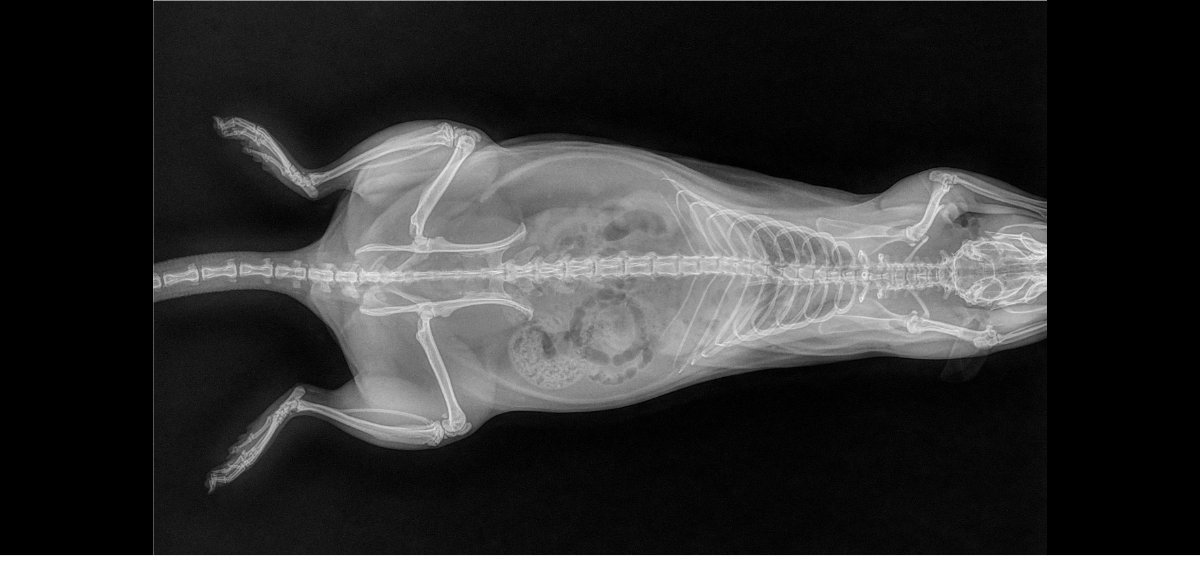

pas de super bonnes nouvelles car les deux miss ont les poumons atteints, si je m'en doutais un peu pour Izar qui ronflait depuis mars (c'est vite parti avec le collyre dans le nez) et respirait une peu trop vite, je suis tombée des nues pour Thari, qui me fait un coup à la Seren : zéro symptôme mais poumons pourris (si seulement elle pouvait avoir la même longévité :siffle:). Les deux pupuces sont donc sous deux antibiotiques (un par injection et un par voie orale) et Izar à en plus un AINS. Contrôle radio prévu dans quelques semaines.

Petites photos des belles et radios en spoil

Thari

Thariprofildroitavril2023.jpg.5c18040e016999d23a3866f24f5c81e8.jpg

Tharifaceavril2023.jpg.6759497e1a95d196154db5a6af44e844.jpg

Thariprofilgaucheavril2023.jpg.297630575b4261f43627592bdb11e17a.jpg

La perpendicularité des fémurs sur la première image me fascine :chut: